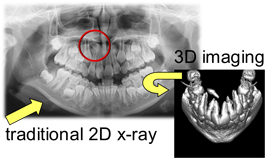

HOWEVER, there is one very important thing that the documentary ROOT CAUSE gets right! There are many patients walking around with active infection in their tooth roots and bone who have ABSOLUTELY NO IDEA that there is any problem whatsoever. We know this is true because we have advanced 3D imaging that allows us to routinely see infections in the tooth and bone that simply cannot be seen in traditional dental X-rays and are asymptomatic.

Because of this, we have been able to help countless patients get rid of active infection in their body quickly and easily. The first step to health is accurate and actionable diagnosis!